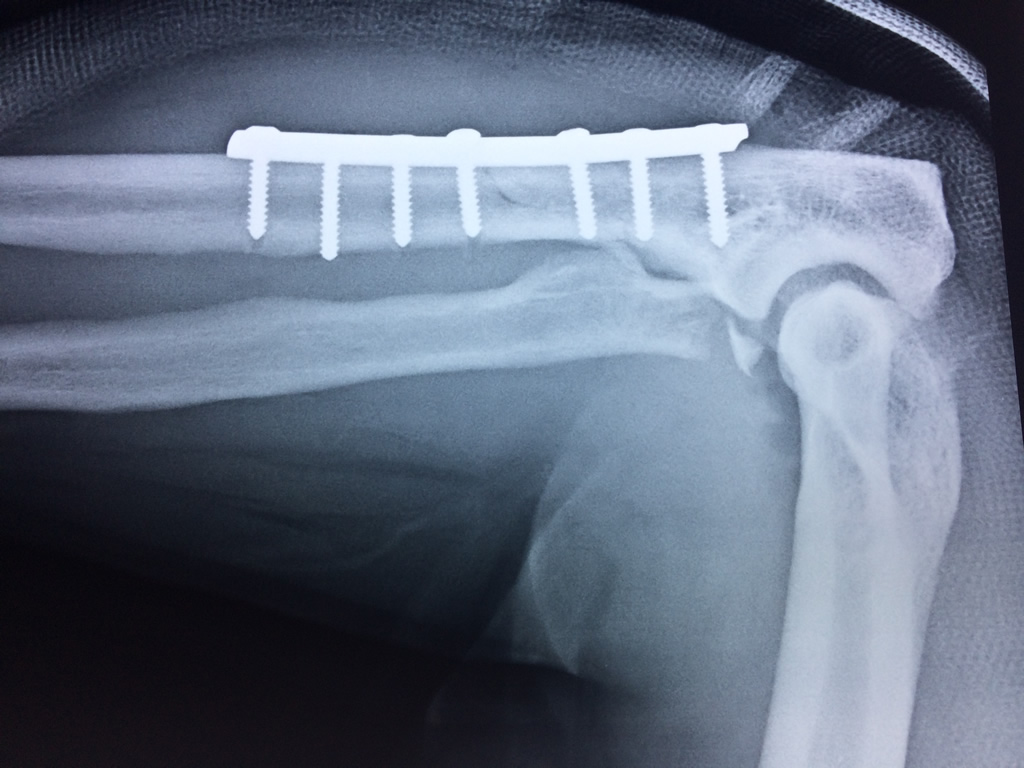

Húmero - Codo

En anatomía humana, la articulación del codo es la que une el brazo con el antebrazo, conectando la parte distal del hueso húmero con los extremos proximales de los huesos cúbito y radio.

La articulación principal que constituye el codo se denomina humero radio-cubital y puede dividirse en dos partes bien diferenciadas, la articulación humero-radial y la humero-cubital.

Por otra parte el cúbito y el radio forman también una articulación entre si en las proximidades del codo, la cual se denomina articulación radio-cubital proximal.